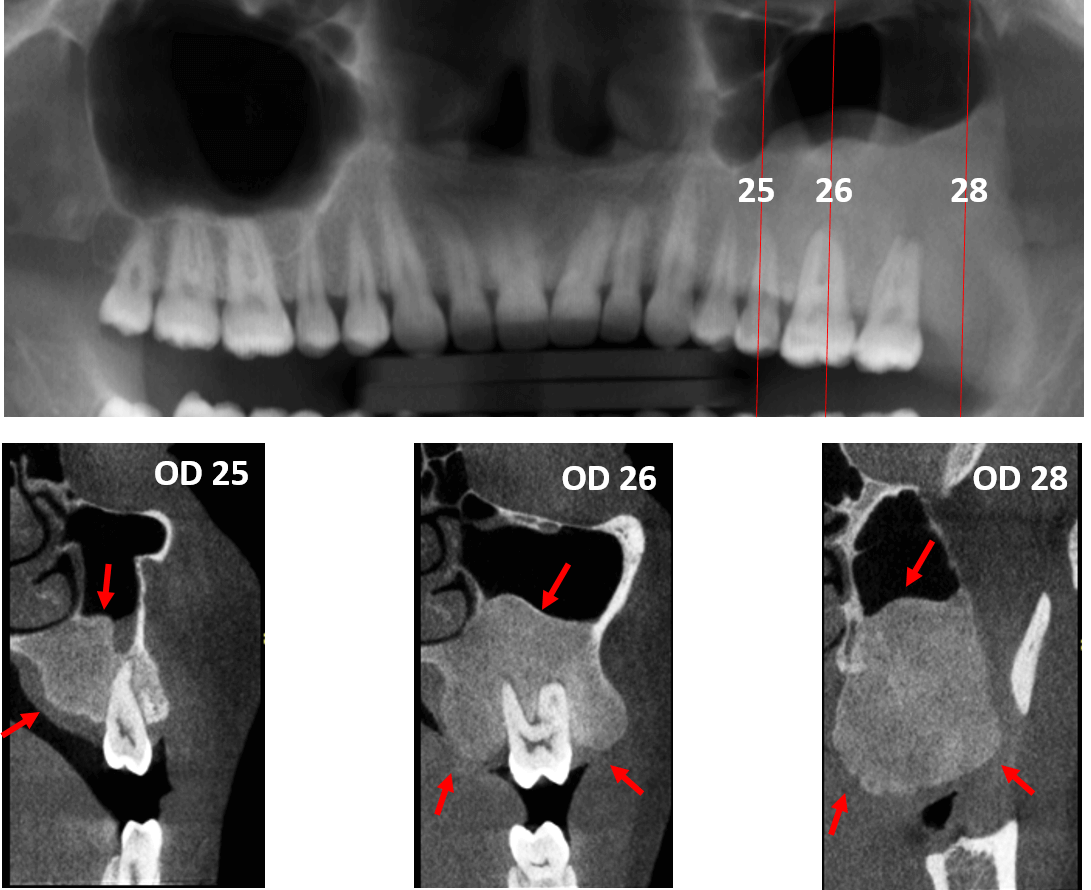

Fig.2

En cortes tangenciales (Fig.2) se observa que dicha lesion se involucra el hueso maxilar a nivel del órgano dentario 24 y se extiende posteriormente hasta la zona del tercer molar (ausente), donde condiciona una proyección en sentido basal. Dicha lesion presenta una densidad relativamente homogénea la cual presenta un patrón de “vidrio esmerilado”. Nótese la extensión de la lesion en el paladar duro (medial).